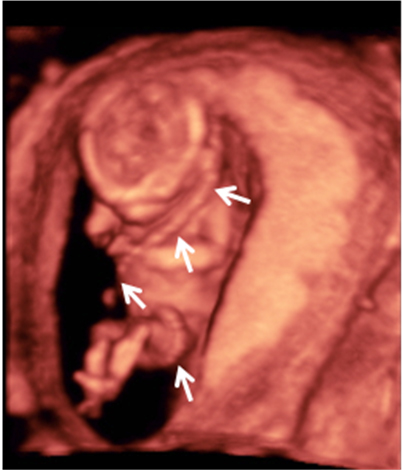

El cordón umbilical es una estructura gelatinosa que suele enrollarse alrededor del feto a medida que este se mueve, especialmente en el primer y segundo trimestre de embarazo. Son perfectamente visibles en las ecografías en 3D.

Feto con cordón umbilical enrollado al cuerpo

Vemos la imagen en tres dimensiones de un feto de 13 semanas de gestación. El cordón umbilical (indicado por las flechas) se asemeja un cinturón de seguridad, ya que pasa del hombro izquierdo a cadera derecha. Luego el cordón continúa por debajo de las piernas para insertarse en el ombligo del bebé.